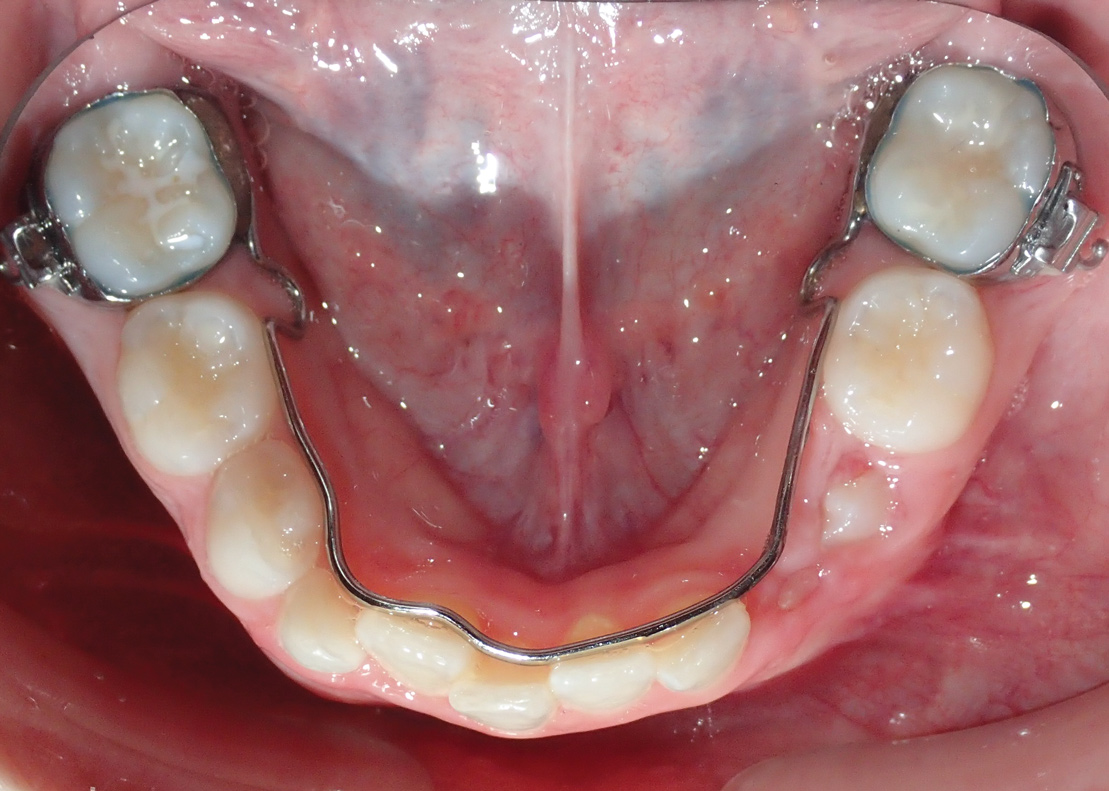

Fig 12. Palatal crib used to passively close bite and break thumb-sucking habit, at delivery (Fig 12), 6 weeks (Fig 13), and 12 weeks (Fig 14).

Figure 12

Tongue and thumb pressures also contribute to a high-vaulted palate, which can lead to mouth breathing (Figure 11).31 Additional risks exist for infection and callus development on the thumb. Ideally, the child should quit this habit by age 4, before permanent occlusal changes develop.32 Quitting can be achieved through positive reinforcement and by offering the child comfort during thumb-sucking triggers. The use of bitterants (eg, Mavala Stop, Thum, Control-It!), which are painted on or rubbed into the thumb, is another option.33 A habit breaker appliance may also be utilized if these techniques are unsuccessful. Devices such as a palatal crib, rake, or bluegrass appliance interfere with the thumb and tongue habits and allow the bite to passively close.34 The author recommends utilizing a habit breaker appliance for 6 to 9 months and maintaining reinforcement for a few months once the habit is eliminated (Figure 12 through Figure 14).